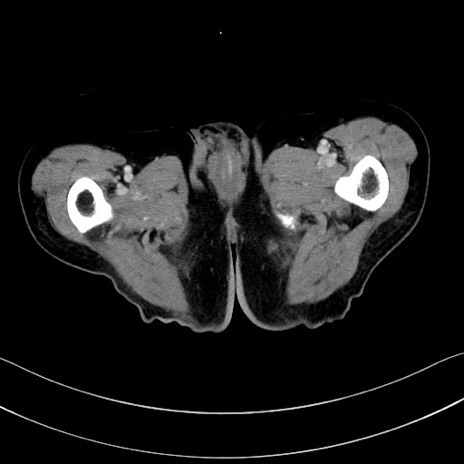

冠状断像

【症例】60歳代男性

【主訴】嘔吐

【現病歴】胃癌にて胃全摘後。食思不振が悪化し、夜中に嘔吐することがある。

【既往歴】胃癌、胃全摘、脾摘、胆摘後

【データ】WBC 5900、CRP 10.56